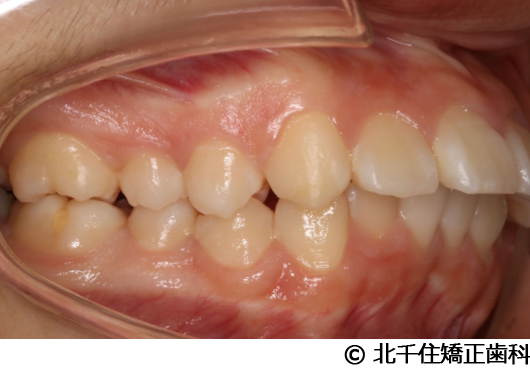

【症例2】上顎前突症

- 治療前

- 治療中

- 治療後

- 治療名

- 上顎前突症

- 費用

- 1,399,000円(税込)

- 期間

- 3年6ヵ月

- 治療回数

- 42回

- 通院頻度

- 1ヵ月ごと

- 年齢・性別

- 19歳10ヵ月・男性(初診時)

治療内容

主訴:出っ歯、口元の突出、横顔をきれいにしたい

骨格性の上顎前突、上下顎第一小臼歯4本及び上顎第二大臼歯を抜歯して矯正用アンカースクリューを併用してワイヤー矯正治療(セラミックブラケット)。

骨格性上顎前突に対し、抜歯および矯正用アンカースクリューを併用した矯正治療により歯列および咬合関係の調整を行った症例である。治療後は保定装置を使用し、歯列および咬合の安定維持を目的として定期的な経過観察を行っている。

※治療結果は個人差があります。

治療を行う上での注意点(リスク・副作用)

歯磨き不良に伴うカリエスや歯周病、顎関節症、歯根吸収など。